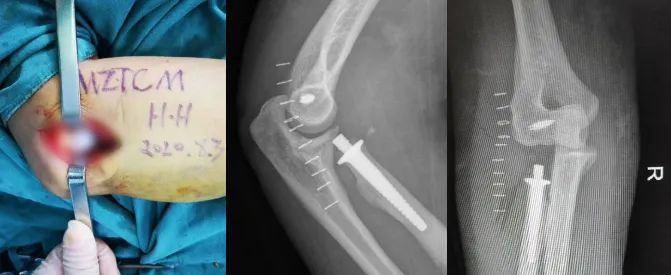

针对该类型骨折,以往常规采取桡骨头切除治疗,但术后常出现因桡骨短缩而导致的肘关节不稳以及下尺桡关节受累情况,后期多疼痛并活动受限。近年来我院上肢骨关节科已成功开展数例人工桡骨头置换手术。故而想到了为患者进行人工桡骨头置换治疗。 ![]() 但是,祸不单行,完善健侧的相关影像资料经测量后发现患者骨骼偏小。常规厂家提供的最小型号桡骨头假体直径为18mm,而患者健侧的桡骨头直径测量不足18mm,且按照该项技术要求,所采用假体直径要比健侧测量值小2mm左右,即直径为16mm假体,术后才能获得满意的活动功能。 针对该困局,患者曾想到放弃对良好功能的追求,行复位内固定的姑息手术。但是我院上肢骨关节科团队仍然为患者深入专研,寻求更好的治疗方案。最后有着多例上肢关节假体置换经验的何晖教授想到了定制一套符合李某自己身体情况的个体化假体进行手术治疗。听到这样的方案,患者及其家属多日的愁眉终于得以舒展。 ![]()

然后积极与假体生成厂家联系,经过设计、加工、运送、手术室灭菌消毒等处理。约1周后终于能为患者实施手术了。手术在精密的操作下,首先将骨粉碎的桡骨头骨块完整取出,再将人工假体安置。手术非常成功,术后第二天李某就按何晖教授的要求在病房进行功能锻炼,术后5天对疗效满意,顺利出院。